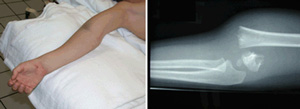

(Left) This child has a severe fracture of the humerus above the elbow. (Right) This x-ray of the fracture shows that the humerus has broken into two parts-a complete displacement.

(Courtesy of Texas Scottish Rite Hospital for Children)